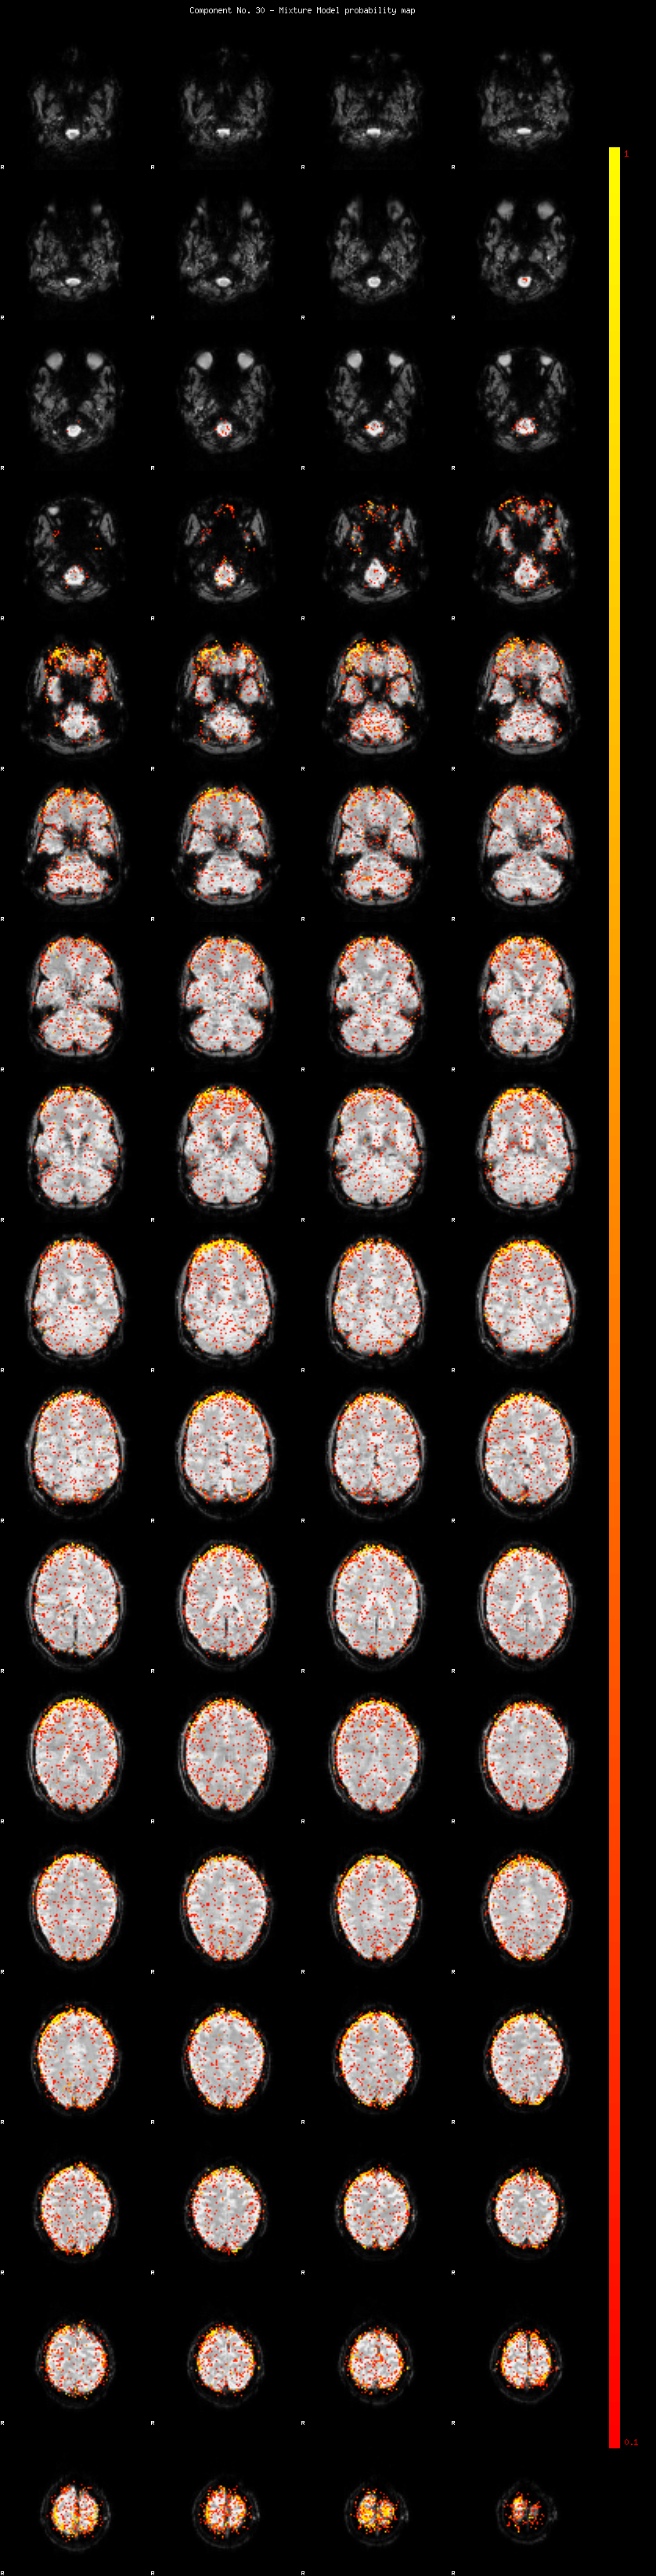

IC_30 Mixture Model fit

Means : -0.000000 2.582019 -2.602038

Vars : 1.000000 2.303348 0.987706

Prop. : 0.934410 0.045671 0.019919